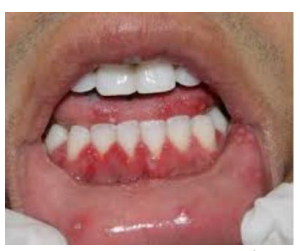

Scurvy (vitamin C deficiency)

Scrobutic gingivitis